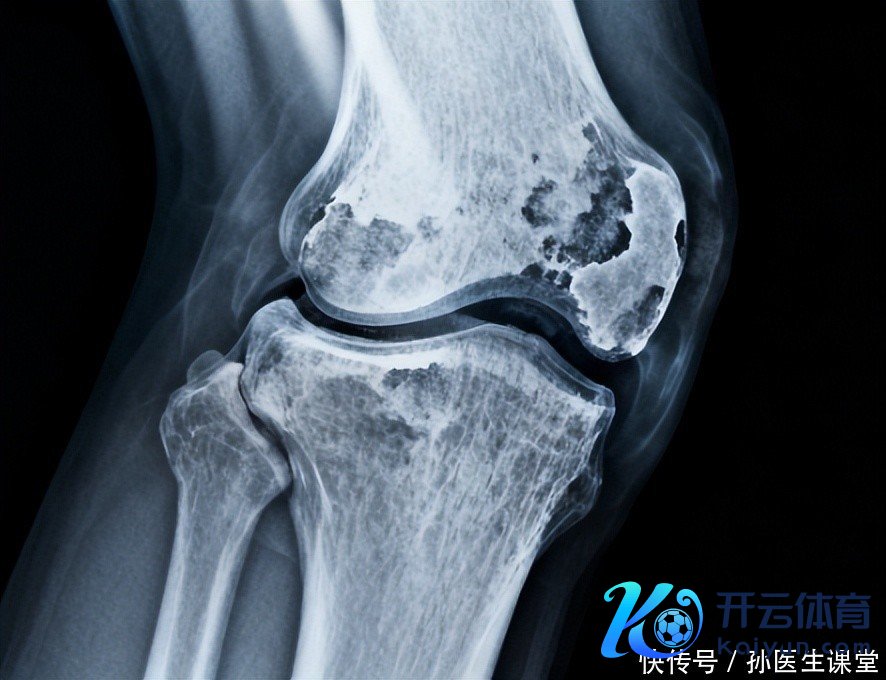

42岁的他曾以为我方还是跟病痛执手言和,没意象一个季节的阴凉让要津再次发出信号。大夫问他,平淡里究竟放在心里的到底是什么?他才发现,真的影响病情的,常常不是某一次用药的得失,而是平淡生存里这三件容易被疏远的小事。

第一件事,药物遵从与按期复诊。许多东说念主会记念反作用、或以为我方嗅觉好就不错停药。效果是一时的自责换来弥远的波动。他的大夫说得很朴实:按时吃药、按时复诊、际遇问题实时不异,哪怕是小调度,也不错让限定更稳妥。提拔并不是盯着痛感强弱,而是把颐养计齐整丝一滴履行好。就像水点石穿,无时无刻的蕴蓄,才有契机把炎症的火苗降下来。

第二件事,规定的融会与得当的休息。他曾以为越多越好,效果把要津蹭热、拉伤,痛感更久。大夫提倡,采选温暖且不竭的融会为主:分布、瑜伽、温暖拉伸,缓缓加多强度,但不要连结冲太猛,融会后给要津富裕休息。正如孟母三迁所示,环境与民风对躯壳的耐受力有潜入影响。褂讪而有序的平淡,常常比一时的用劲更有用。

第三件事,饮食、就寝与情谊的笼统料理。平淡小细节也能放大或扼制炎症信号:过多糖分和加工食物、浓重食物可能让体内炎性响应更敏锐;就寝不及和弥远压力也会让疾苦更容易出现。于是他驱动节约单作念起:晚餐以蔬果、全谷和瘦肉为主,减少高糖高脂的招引;固定工夫睡觉,给我方留几分钟减轻的工夫。这么的蜕变看似眇小,弥远提拔却像水点渐渐穿过石头,渐渐蜕变了躯壳的“责任相貌”。